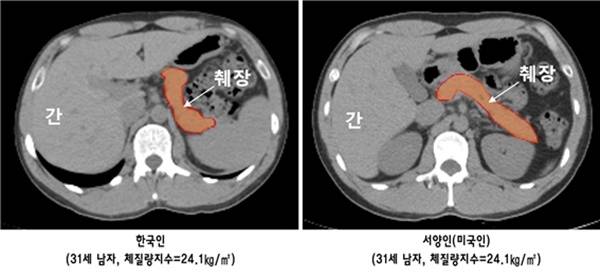

임수 교수팀은 최첨단 컴퓨터 단층촬영(CT)을 통해 한국인과 서양인의 췌장 용적(볼륨) 및 췌장 내 지방 함량을 비교했다. 이와 함께 췌장 베타세포에서의 인슐린 분비능과 당대사능을 측정해 췌장의 크기 및 지방함량과 인슐린 분비능 사이의 관련성에 대해 분석하고자 했다.

연구는 체격이 유사한 30대 연령의 한국인과 서양인 각 43명을 대상으로 진행됐다. 우선 기본 혈액 검사 결과 공복혈당 및 당화혈색소 수치는 양쪽 그룹 사이에 차이가 없었으며, 마찬가지로 총콜레스테롤, 중성지방, HDL-콜레스테롤, LDL-콜레스테롤 모두 그룹 간 차이가 없었다.

그러나 췌장의 용적을 비교한 결과 한국인이 서양인에 비해 췌장의 크기가 12.3% 정도 작았으며, 오히려 췌장 내 침착된 지방의 양은 서양인에 비해 22.8% 더 많은 것으로 확인됐다.